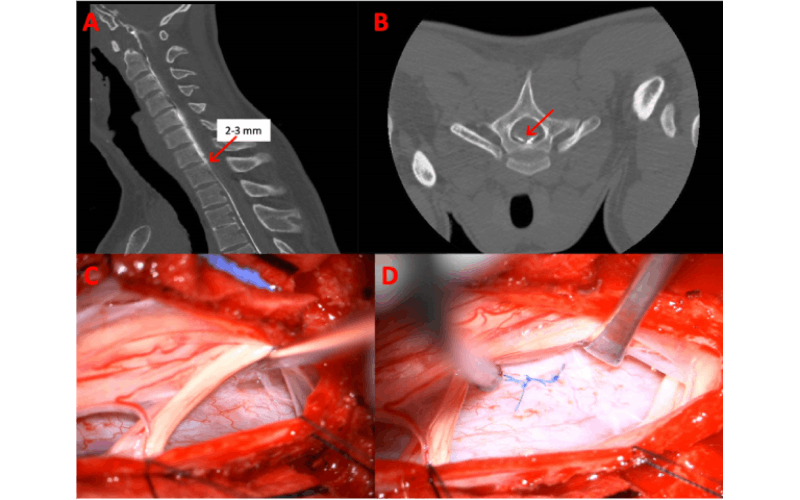

Images from a hyperdynamic multiphase prone CT myelogram

Images from a hyperdynamic multiphase prone CT myelogram. Contrast can be seen to course caudally within the subarachnoid space (arrow, A) with inferior-most divergence/extravasation of contrast into the epidural space identified at the C7-T1 level compatible with the "fork in the road" (arrow, B) at the level of a small osteophyte at the posterior margin of the C7-T1 disc space, which is essentially midline. Ventral epidural contrast is seen extending cranially to the craniocervical junction. (C) Intraoperative photograph showing a transdural exposure of a defect in the ventral dura. (D) Intraoperative photograph showing suture repair of the dural defect.